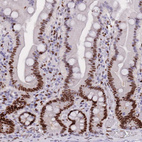

Immunohistochemical staining of human gastrointestinal, lymphoid tissues, pancreas and testis using Anti-NASP antibody HPA030520 (A) shows similar protein distribution across tissues to independent antibody HPA028136 (B).